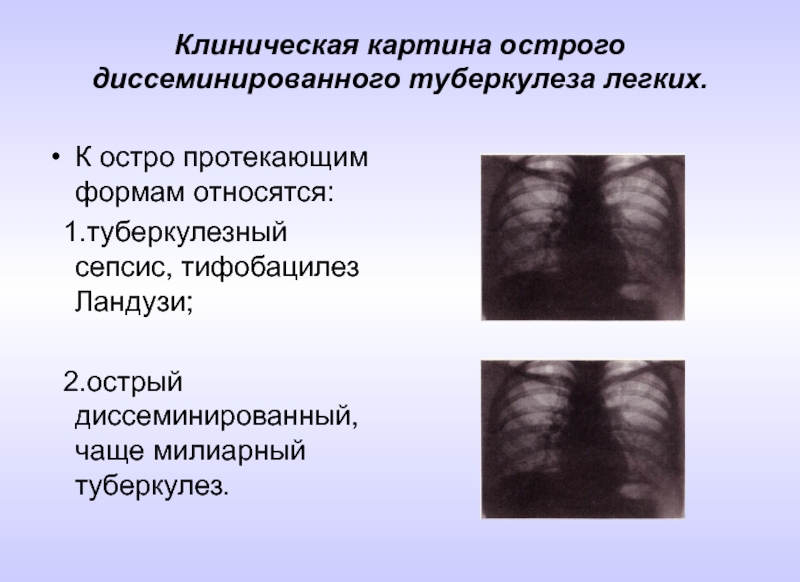

В клинической картине острого гематогенно диссеминированного туберкулеза преобладает